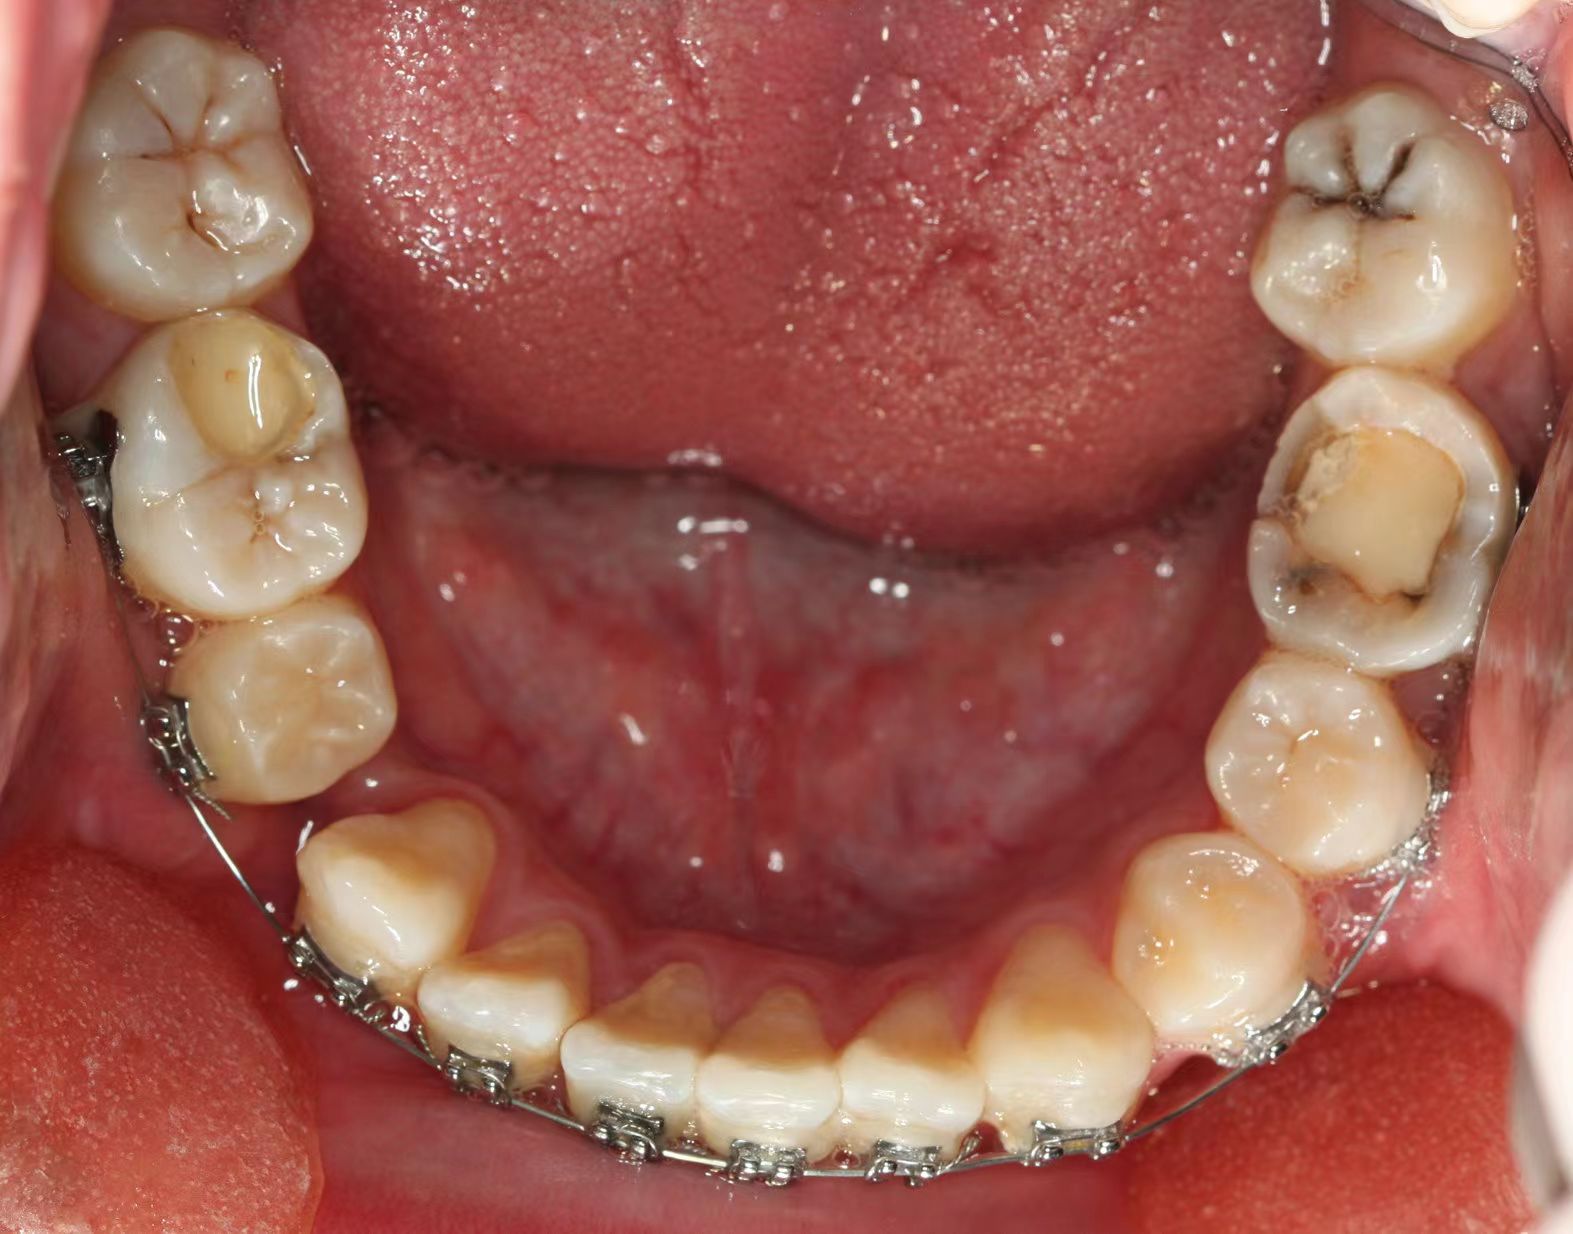

情况:不接受外科手术,在当地做了1年半的矫治,遇到困难无法进行。由外地正畸同行推荐来上海寻求非手术矫治的二手病例。武广增老师接收时的错合畸形情况,呈现严重的骨性反合偏合及侧方开合(图1-图10)。由于推荐其去口腔医院接受正颌外科手术遭到拒绝,武广增老师通过专业的检查、分析,制定一套详细的治疗计划,采用了磨牙推进器技术、武式辅弓技术等特色正畸手段获得明显效果(图2-1~图2-9)。治疗结束后也拍摄了相关照片(图3-1~图3-9)。

矫治前

图1